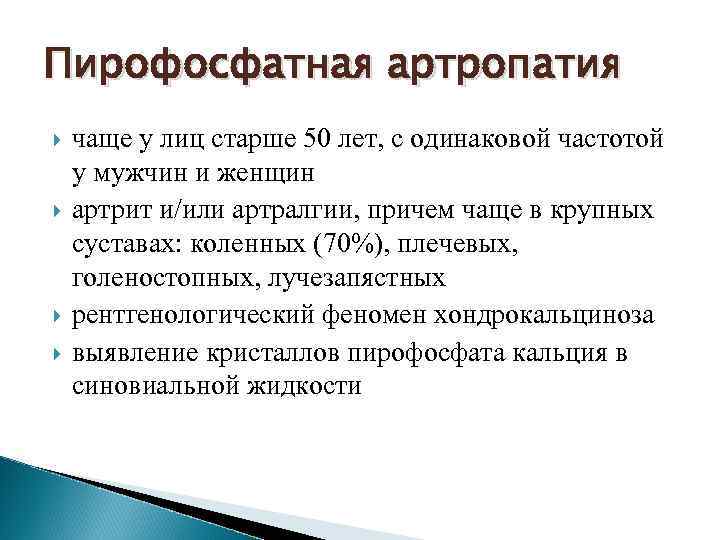

Пирофосфатная артропатия чаще у лиц старше 50 лет, с одинаковой частотой у мужчин и женщин артрит и/или артралгии, причем чаще в крупных суставах: коленных (70%), плечевых, голеностопных, лучезапястных рентгенологический феномен хондрокальциноза выявление кристаллов пирофосфата кальция в синовиальной жидкости